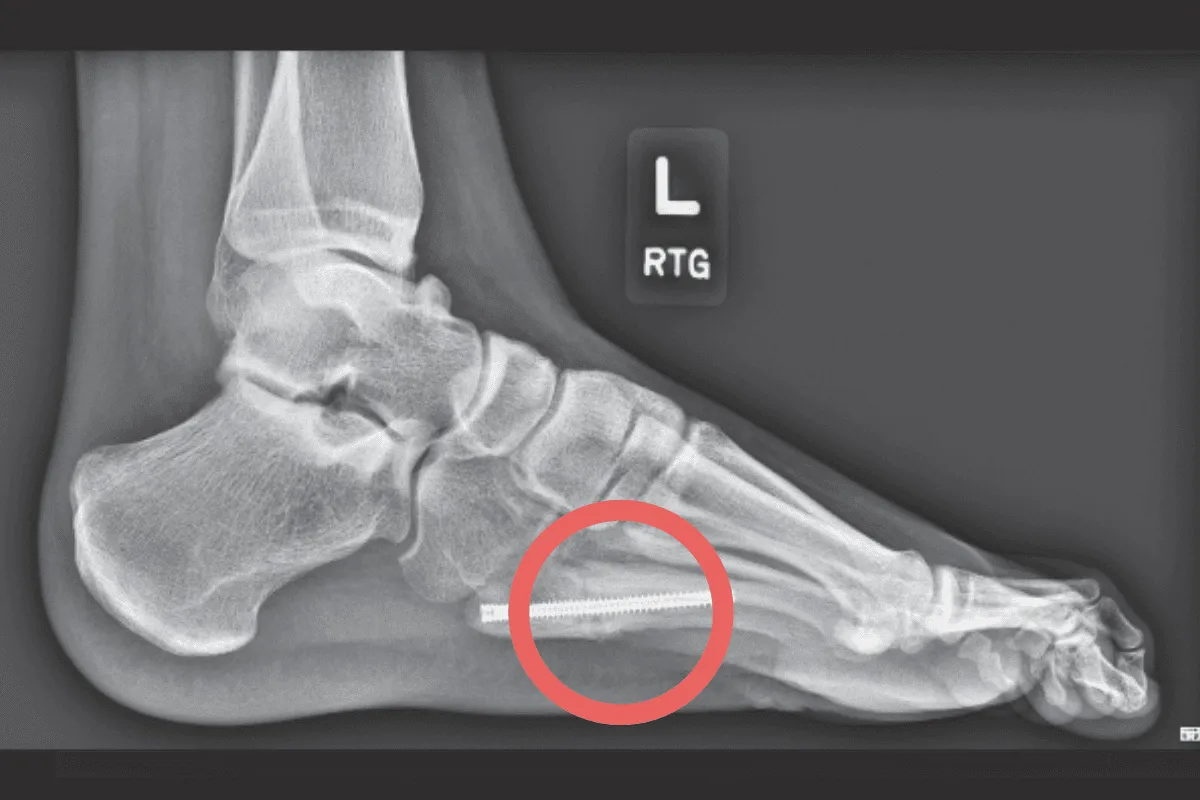

Sytuacja wygląda zupełnie inaczej przy skomplikowanych złamaniach wieloodłamowych, gdzie kość rozpadła się na wiele fragmentów, złamaniach śródstawowych, które uszkadzają powierzchnie stawowe, czy złamaniach otwartych, gdzie doszło do przerwania ciągłości skóry. Te urazy niemal zawsze wymagają leczenia operacyjnego, często z zespoleniem odłamów za pomocą płytek i śrub. Taka interwencja chirurgiczna, choć niezbędna, automatycznie wydłuża proces gojenia i rehabilitacji, wprowadzając dodatkowe wyzwania, takie jak gojenie się rany pooperacyjnej i ryzyko infekcji.

Leczenie operacyjne natomiast, choć pozwala na precyzyjne nastawienie odłamów i często wcześniejsze rozpoczęcie delikatnych ruchów, niesie ze sobą ryzyko powikłań związanych z samą operacją. Dodatkowo, po operacji konieczne jest uwzględnienie czasu na gojenie się tkanek miękkich i rany. W obu przypadkach, fizjoterapeuta musi ściśle współpracować z lekarzem prowadzącym, aby dostosować plan rehabilitacji do specyfiki zastosowanej metody leczenia i aktualnego stanu zrostu kostnego.